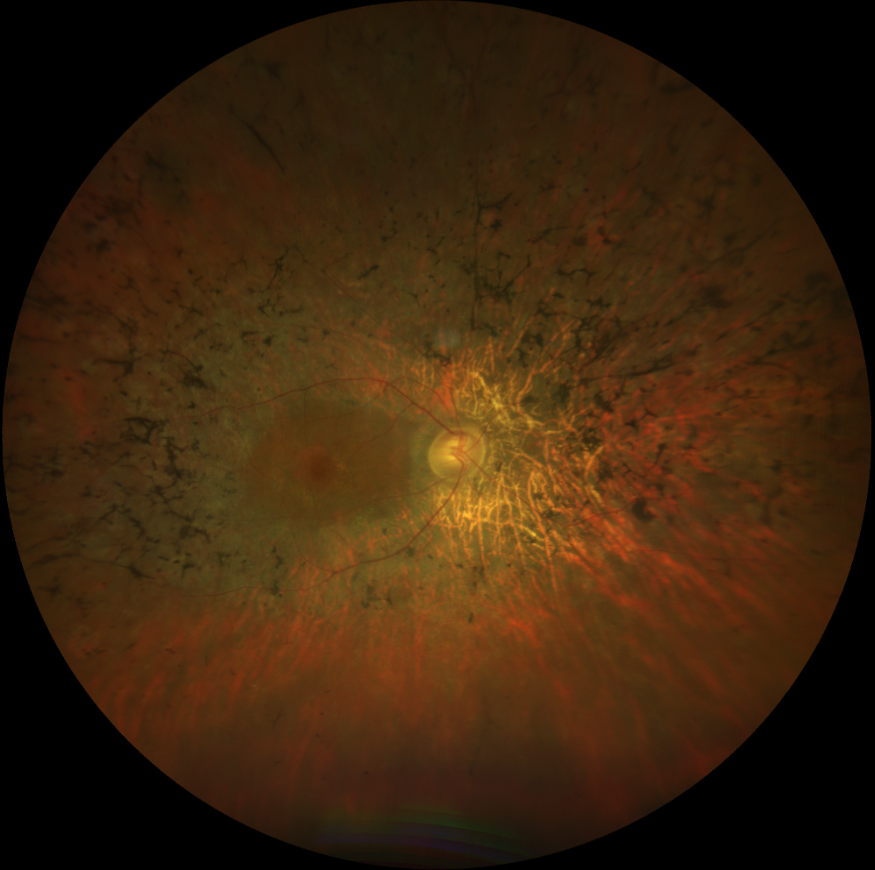

Sağ gözde beş gündür artan görme azlığı olan 30 yaşındaki kadın hastanın renkli ...